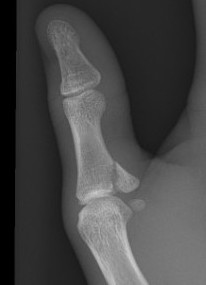

X-ray

Bony avulsion

1. Small fragment pulled away from proximal phalanx

2. Large intra-articular fracture involving >1/4 articular surface

3. Salter Harris III in pediatric population